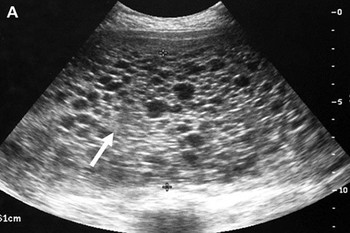

ครรภ์ไข่ปลาอุก (Molar pregnancy หรือ Hydatidiform mole) คือ การตั้งครรภ์ที่ผิดปกติชนิดหนึ่งที่มีอาการเริ่มแรกเหมือนการตั้งครรภ์ทั่วไป คือ ประจำเดือนขาดและมีอาการแพ้ท้อง (บางรายอาจมีอาการแพ้ท้องอย่างรุนแรง คือ มีอาการคลื่นไส้อาเจียนมากกว่าปกติหลายเท่า) มีเลือดออกทางช่องคลอด แต่สีเลือดที่ออกมาจะไม่ใช่สีแดงสด แต่จะเป็นสีน้ำตาลคล้ำ ๆ คล้ายเลือดเก่า (อาจจะออกเพียงเล็กน้อยหรือออกมากก็ได้ ซึ่งการมีเลือดออกในครรภ์ไข่ปลาอุกนี้ก็เป็นการแท้งชนิดหนึ่งนั่นเอง) นอกจากจะมีเลือดออกมาแล้ว บางครั้งยังอาจมีเม็ดกลม ๆ ใส ๆ คล้ายกับไข่ปลาอุกหลุดปนออกมาทางช่องคลอดด้วย

ไข่ปลาอุก หรือ ท้องไข่ปลาอุก การตั้งครรภ์ชนิดนี้ส่วนใหญ่แล้วมักจะไม่มีตัวเด็ก เนื่องจากตัวเด็กไม่เจริญเติบโตตั้งแต่อายุได้ 3-5 สัปดาห์แล้ว แต่ส่วนที่ออกมาให้เห็นเป็นเม็ด ๆ นั้น คือส่วนของเนื้อรกที่มีการเจริญผิดปกติจนกลายเป็นเนื้องอกคล้ายถุงน้ำอยู่เต็มไปหมดภายในโพรงมดลูก ส่วนมากจะเป็นเนื้องอกชนิดไม่ร้ายที่ไม่มีอันตรายร้ายแรง มีเพียงส่วนน้อยเท่านั้นประมาณร้อยละ 2 ที่อาจกลายเป็นเนื้อร้ายหรือมะเร็งเยื่อรก ซึ่งอาจลุกลามและแพร่กระจายตามกระแสเลือดไปทั่วร่างกายได้ โดยโรคครรภ์ไข่ปลาอุกนี้มักเกิดขึ้นในระยะแรก ๆ ของการตั้งครรภ์ หรือในช่วงประมาณสัปดาห์ที่ 10-16 ของการตั้งครรภ์

ตามปกติแล้วภายหลังการผสมกันระหว่างไข่กับเชื้ออสุจิก็จะมีตัวอ่อนเกิดขึ้น ซึ่งตัวอ่อนนี้จะมีการพัฒนาต่อไปเป็นรกและเป็นตัวเด็ก แต่จากการศึกษาทางการแพทย์พบว่า การตั้งครรภ์ของคุณแม่บางรายไม่เป็นเช่นนั้น เนื่องจากเซลล์ส่วนที่จะเป็นรกนั้นมีการเจริญเติบโตอย่างรวดเร็ว ในขณะที่เซลล์ส่วนที่จะกลายเป็นตัวทารกกลับตายไป จึงเหลือแต่ส่วนที่เป็นรก และรกนั้นสามารถสร้างน้ำขึ้นมาได้อย่างมากมาย จึงทำให้มองเห็นเป็นเม็ดใส ๆ คล้ายไข่ปลาอุก

ในปัจจุบันวงการแพทย์ยังไม่สามารถหาสาเหตุว่าการตั้งครรภ์ไข่ปลาอุกนั้นเกิดจากสาเหตุอะไร แพทย์บางท่านเชื่อว่าน่าจะเกิดจากกรรมพันธุ์ บ้างก็เชื่อว่าน่าจะเกิดจากการขาดสารอาหารบางอย่าง หรืออาจเกิดจากการสร้างฮอร์โมนบางชนิดที่ผิดปกติ สรุปก็คือ ยังไม่ทราบแน่ชัดแต่เท่าที่ทราบได้ก็คือ เป็นเนื้องอกของเนื้อรกชนิดหนึ่งที่มีการแบ่งตัวมากผิดปกติ ซึ่งเกิดจากการปฏิสนธิกันระหว่างไข่กับเชื้ออสุจิที่มีโครโมโซมผิดปกติ (ไข่ของคุณแม่ไม่มีโครโมโซมเพศ (โครโมโซม X) เมื่อถูกผสมจากเชื้ออสุจิของคุณพ่อ โครโมโซมของตัวอ่อนนี้จึงเป็นโครโมโซมของคุณพ่อเองทั้งหมด) ทำให้ไม่สามารถเจริญเติบโตไปเป็นตัวอ่อนของมนุษย์ตามปกติได้ แต่จะเจริญผิดปกติเป็นถุงน้ำเล็ก ๆ จำนวนมากอยู่ภายในโพรงมดลูก